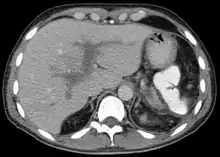

Portal vein thrombosis on computed tomography (left) and cavernous transformation of the portal vein after 1 year (right)

The diagnosis of portal vein thrombosis is usually made with imaging confirming a clot in the portal vein; ultrasound is the least invasive method and the addition of Doppler technique shows a filling defect in blood flow. PVT may be classified as either occlusive or nonocclusive based on evidence of blood flow around the clot.[5] An alternative characterization based on site can be made: Type 1 is limited to the main portal vein, Type 2 involves only a portal vein branch (2a, or 2b if both branches are affected), and Type 3 if clot is found throughout both areas.[8] Determination of condition severity may be derived via computed tomography (CT) with contrast, magnetic resonance imaging (MRI), or MR angiography (MRA). Those with chronic PVT may undergo upper endoscopy (esophagogastroduodenoscopy, EGD) to evaluate the presence of concurrent dilated veins (varices) in the stomach or esophagus.[3] Other than perhaps slightly elevated transaminases, laboratory tests to evaluate liver function are typically normal.[1] D-dimer levels in the blood may be elevated as a result of fibrin breakdown.